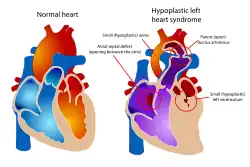

Examples of congenital cardiac malformations in which this procedure may be used include hypoplastic left heart syndrome, tricuspid atresia, double-inlet left ventricle and double-outlet right ventricle.[3][1] The natural history of congenital univentricular cardiac malformations results in cyanotic heart failure at an early age. Staged palliation through the BDG shunt and Fontan procedure has allowed these patients to live into adulthood.[4]

Pulmonary hypertension (moderate to severe) is a relative contraindication to the bidirectional Glenn.[5] This is because pulmonary vascular resistance is too elevated to allow sufficient oxygenation.[5] In physiologic parameters, this includes elevated pulmonary vascular resistance, stiff ventricle tissue, and dysfunction of the atrio-ventricular valve. In patients with hypoplastic left heart syndrome, obstruction of blood flow at the atrial septum should be examined and corrected.[1]